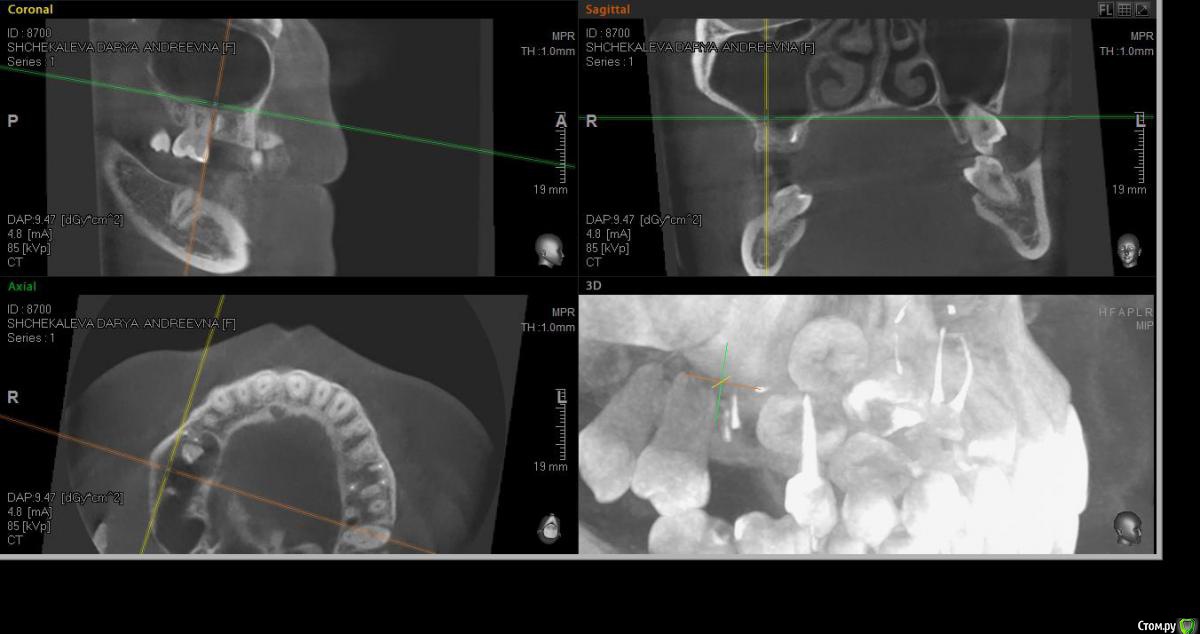

alekszander Опубликовано 14 марта, 2016 Поделиться Опубликовано 14 марта, 2016 Собственно вопрос кто сам доставал какие особенности? Или все же лучше к ЛОРу через эндоскоп?Боюсь только что корень с мембраной создал спайку и во время удаления просто порву мембрану.Дальние корни попробую аккуратно периотомом убрать. Ссылка на комментарий

faity Опубликовано 14 марта, 2016 Поделиться Опубликовано 14 марта, 2016 Можно со стороны альеолярки влезть, можно сразу окно выпилить.Для начала делаете доступ для визуализации, визуализируете апекс, потом аккуратно цепляете апикально чтобы мембрану не порвать, подойдёт кюретажка Лукаса маленькая 2мм и как с кистой или грануляцией вылущиваете. Если протолкнули- снимок и окно в проекции. 1 Ссылка на комментарий

alekszander Опубликовано 14 марта, 2016 Автор Поделиться Опубликовано 14 марта, 2016 Если протолкнули- снимок и окно в проекции.Что имеете ввиду если протолкнул, при попытке достать корень толкнул его глубже? И не совсем понял про снимок, помню читал тему, что его подшивают, но не совсем понял как в в данном случае - уложить и потом отдельно доставать? Ссылка на комментарий